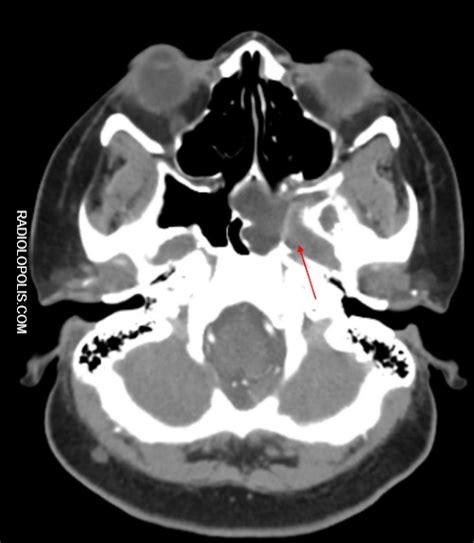

Image of the Month—Quiz Case. | Cardiology | JAMA Surgery ...

Image of the Month—Quiz Case. | Cardiology | JAMA Surgery ... from jamanetwork.com